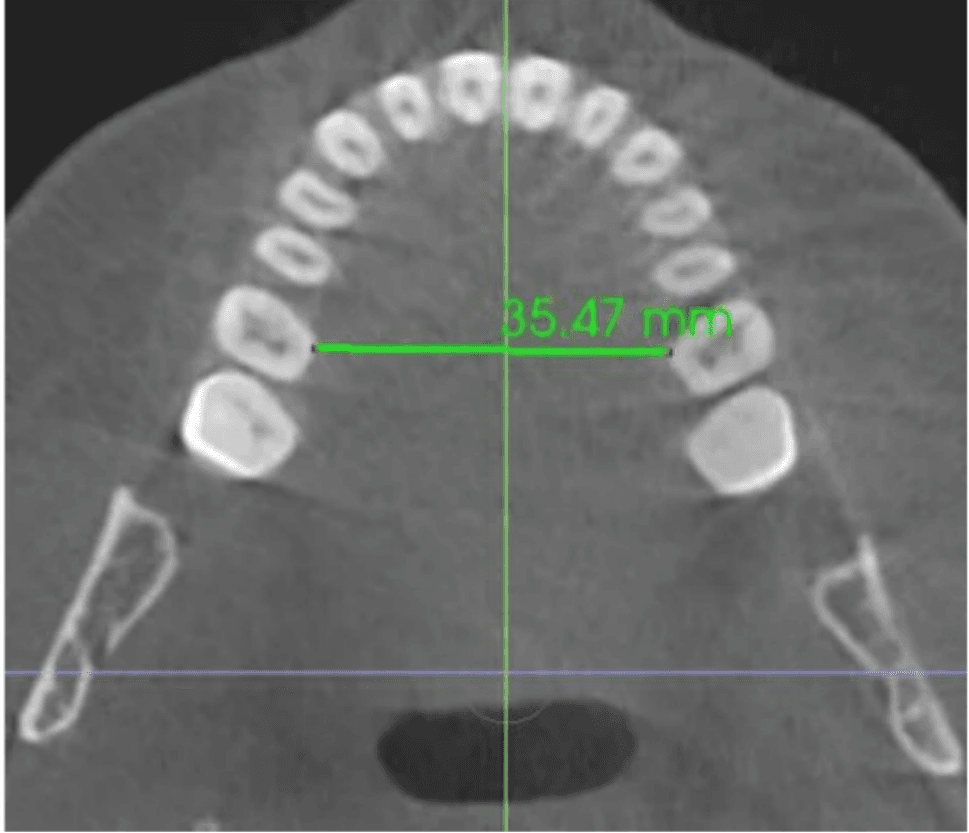

Dr. Tara Griffin is a Vivos provider who underwent treatment herself. She was diagnosed with moderate obstructive sleep apnea in 2011, with an AHI of 24 events per hour. What distinguishes her case is the depth of documentation: her progress was tracked not only by sleep studies but by direct measurement of her dental arch, the structural width of the upper jaw, over the course of eight years. Her arch measured 31.5 millimeters before treatment. By 2013, after approximately 10 to 15 months of treatment, it had expanded to 35.5 millimeters. At her 2019 follow-up, 37.5 millimeters.

Jaw Width - 35.5mm

Post-Treatment, 2013